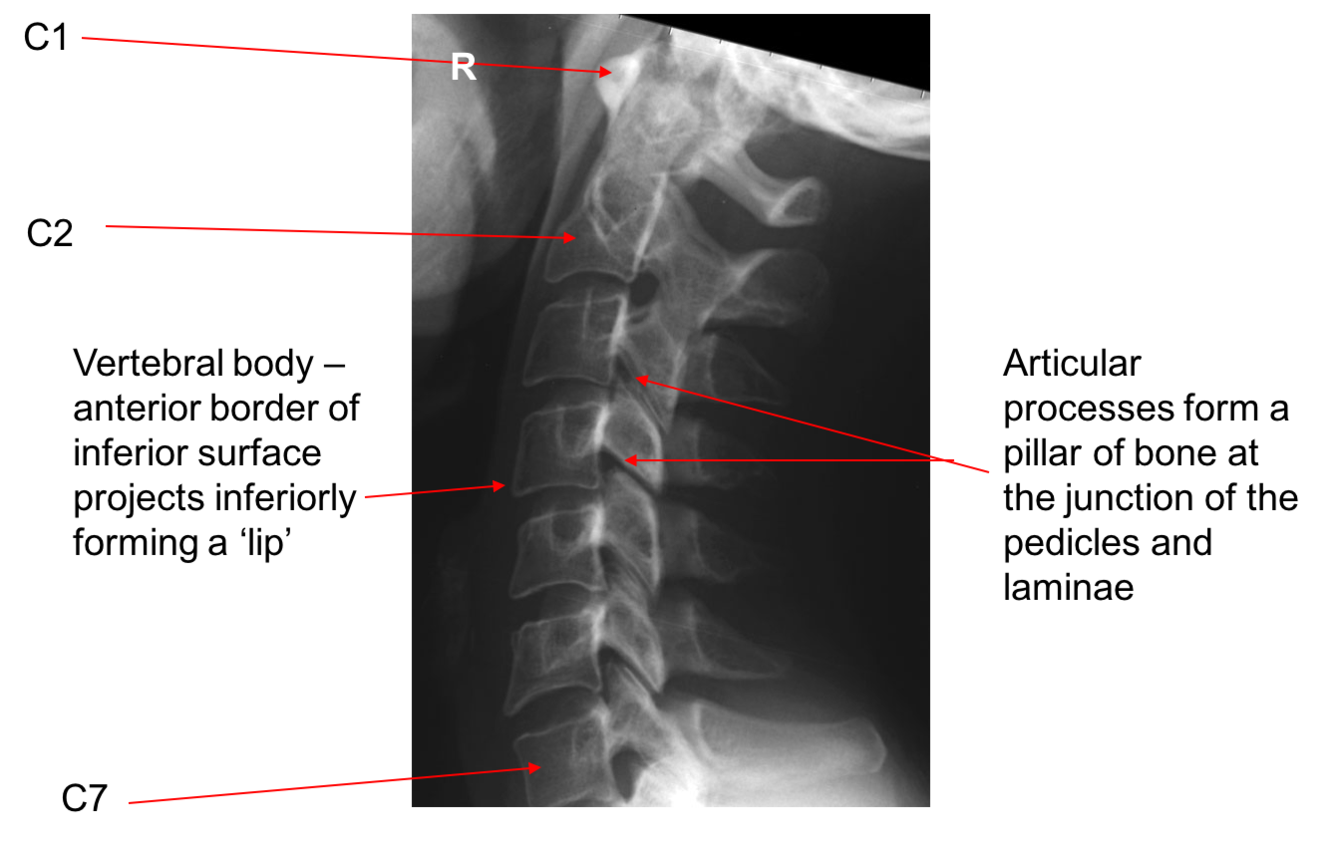

Label image